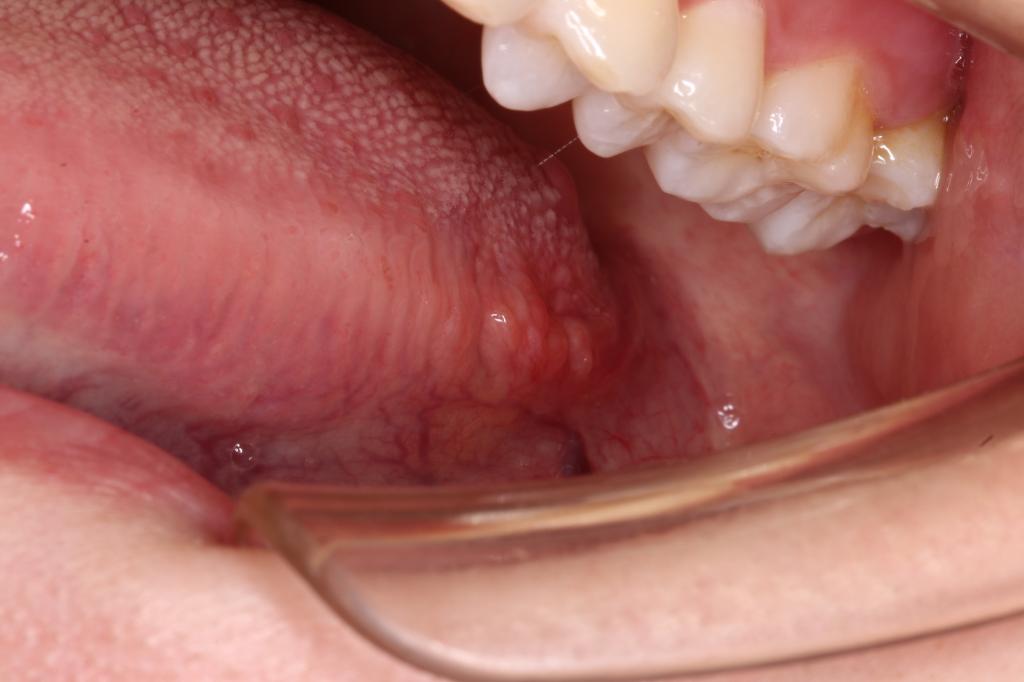

舌根这个不是肿瘤喔,这是叶状乳头(每个人都有的正常结构)